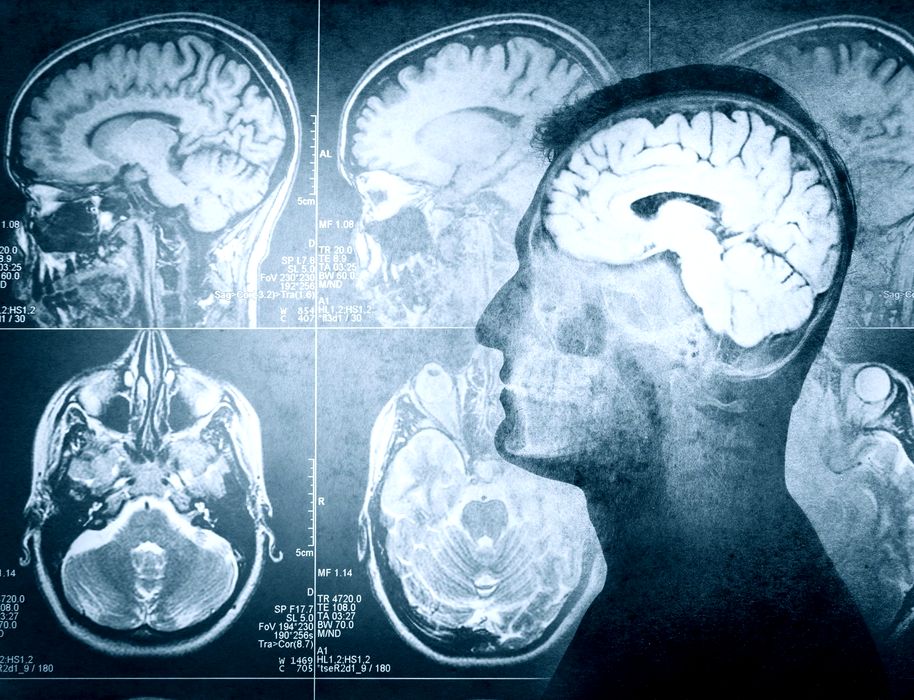

Ce s-a întâmplat după ce o femeie a auzit voci care îi spuneau că are o tumoare pe creier?

În 1984, o femeie perfect sănătoasă a început, brusc, să audă voci care îi spuneau că are o tumoare pe creier. Experiența a speriat-o profund, făcând-o să se teamă pentru sănătatea ei mintală, așa că […]